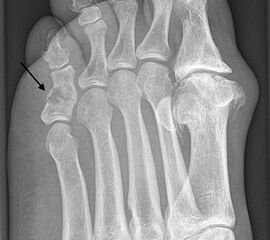

Das Enchondrom ist der häufigste Knochentumor im Bereich von Hand und Fuß und nach dem Osteochondrom der zweithäufigste gutartige Knochentumor überhaupt. Die geschlechtliche Verteilung ist ausgeglichen, Enchondrome finden sich meist bei Patienten zwischen 20-40 Jahren. Dieser chondrogene Tumor verhält sich meist asymptomatisch, kann aber durch eine Knochenexpansion und Schwellung sowie Spontanfrakturen (Abb. 17) auffallen. Radiologisch zeigen sich in der Regel gut abgrenzbare Osteolysen, Matrixverkalkungen sind typisch aber nicht obligat. Die MRT zeigt typischerweise eine annähernd flüssigkeitsäquivalente Signal­qualität mit niedrigen Signalintensitäten in T1 und hoher Signalgebung in T2, die Binnen­struktur weist eine für chondrogene Tumoren typische Lobulierung mit KM-Aufnahme auf.

Im Gegensatz zu Osteochondromen ist die Lage von Enchondromen nicht auf die Metaphyse beschränkt. Sie finden sich auch im Bereich der Epi- und Diaphysen. Die kurzen tubulären Knochen der Metatarsalia und Phalangen sind bevorzugt betroffen. Hier findet sich die Läsion typischerweise im Bereich der proximalen Phalangen oder distalen Metatarsalia, eine Ausbreitung auf die gesamte Diaphyse ist von hier aus jedoch nicht ungewöhnlich. Die Möglichkeit einer malignen Entartung (Chondrosarkom) ist im Bereich der Metatarsalia und Phalangen im Vergleich zu den langen Röhrenknochen und platten Knochen extrem selten 33. Die übliche Therapie besteht in einer gründlichen Curettage. Je nach Größe des Defekts und Schwächung der Kortikalis kann die Transplantation eines stabilisierenden kortiko­spongiösen Spans notwendig werden. Zusätzliche osteosynthetische Verfahren sind nur selten erforderlich.